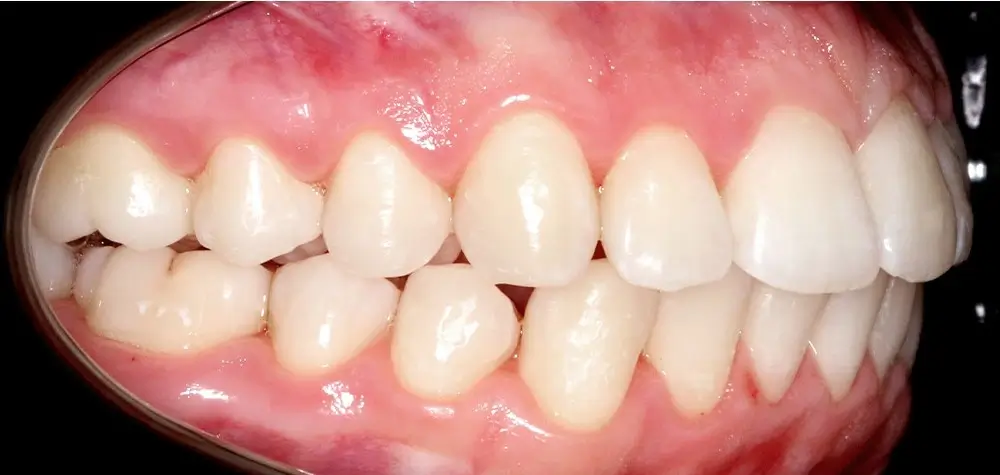

Скученность - Кейс 10

Эффективность устранения дефекта прикуса посредством элайнеров FlexiLigner.

Результаты лечения